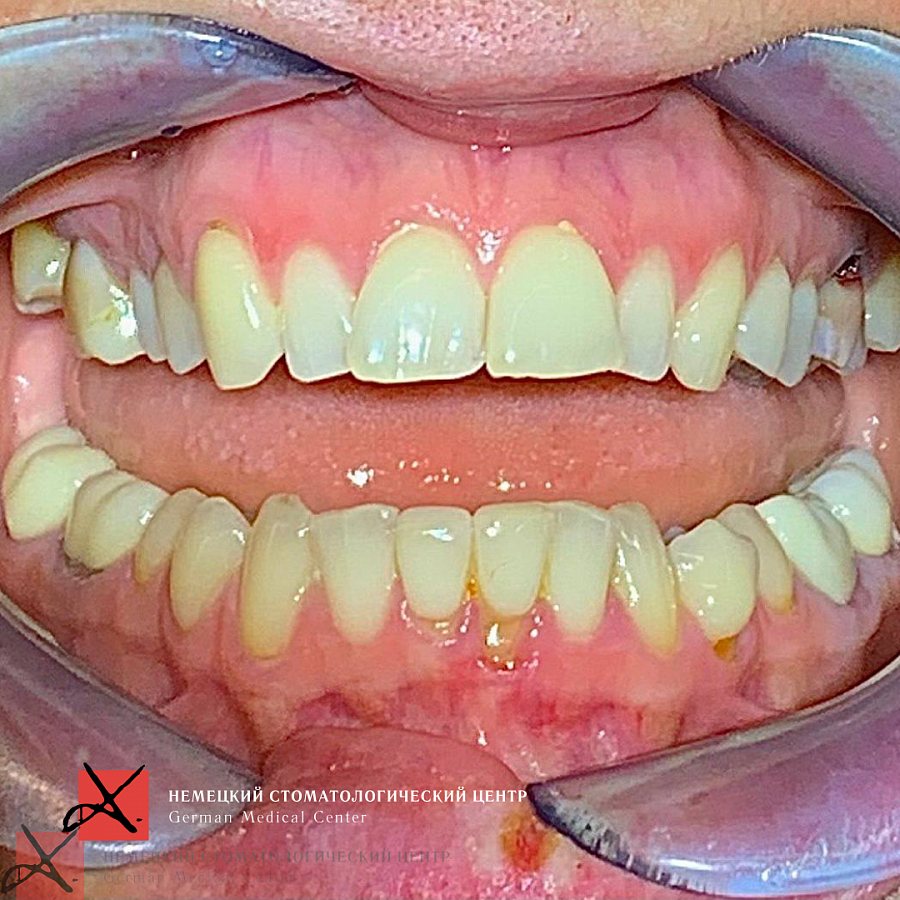

Сначала было проведена санация полости рта. Затем а ортодонтическое лечение для восстановления высоты прикуса.

С эстетической частью справились за счёт протезирования винирами в естественной форме и в естественном цвете.

Результат получился отличный! Пациентка очень довольна!